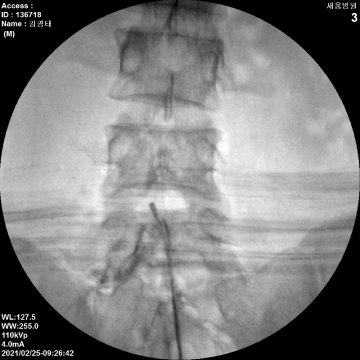

신경성형술

2020.01.21

2020.10.06

2021.02.25